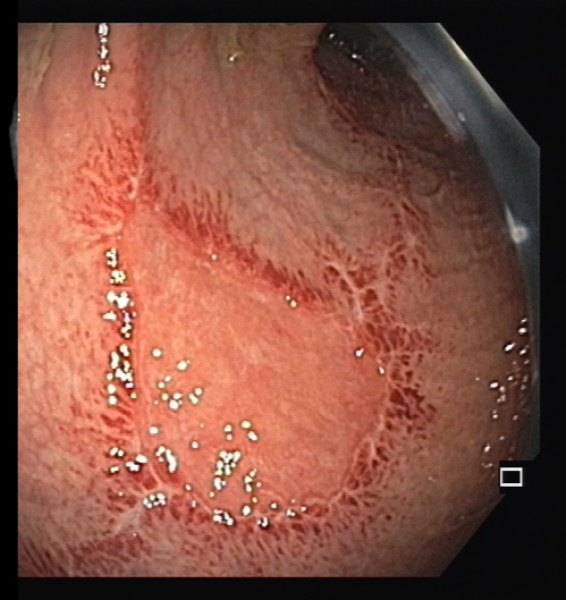

Spontaneous esophageal perforation: an uncommon complication of eosinophilic esophagitis

Fotografia